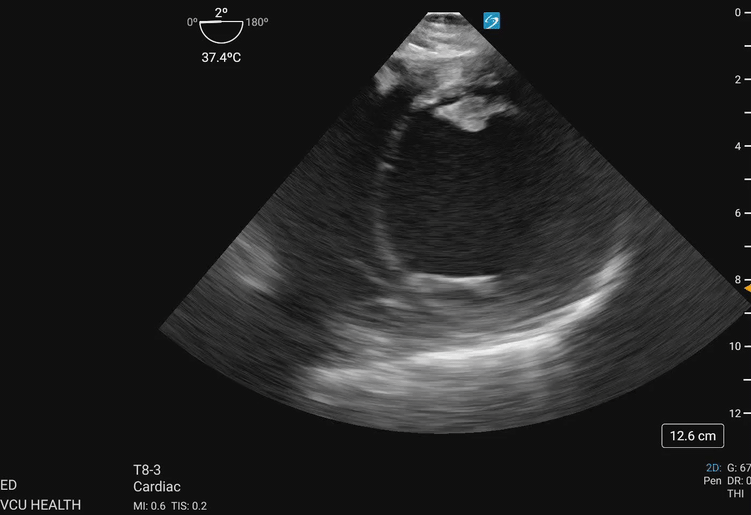

In the focused approach utilized in resuscitative TEE, evaluation of regional wall motion abnormalities in the major vascular territories of the left anterior descending (LAD), left circumflex (LCx), and right coronary artery (RCA) can be performed using the TG SAX view at the level of the midpapillary plane. To obtain this view, the operator will advance the TEE probe to an approximate depth of 40cm from the incisors, set the omniplane angle between 0-20 degrees, and anteflex the probe sufficiently to obtain the view demonstrated in Figure 1 and Figure 2. With slight adjustments in the depth of insertion further assessment of the base and apex of the left ventricle can be obtained.

Transgastric_Figure_2_compressed.gifFigure 2. Transgastric midpapillary view demonstrating the left ventricle and papillary muscles visualized at approximately 40cm depth from the incisions, omniplane between 0-20 degrees, and anteflexion of the probe. This patient demonstrates global left ventricular hypokinesis. Image courtesy of Lindsay Taylor, MD.

Transgastric_Figure_3a_compressed.gifFigure 3a. Walls of the left ventricle as seen on TGSAX with vascular territories. The left ventricle here demonstrates global hypokinesis rather than pathology isolated to one vascular territory. Image courtesy of Lindsay Taylor, MD.